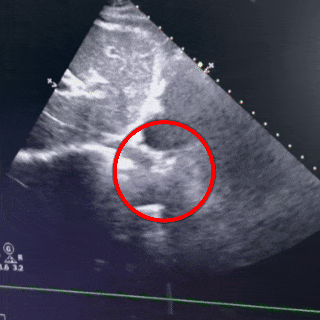

经胸超声描述:房间隔可见回声中断,胸骨旁大动脉短轴切面回声中断约14.0mm,断端与主动脉根部无明显边缘回声,心尖四腔心切面回声中断约16.8mm(除去软边),断端距二尖瓣前叶室间隔附着点约17.8mm,断端距房顶约11.7mm,房间隔全长约49.8mm,剑下双房心切面回声中断约13.3mm,剑下双房、双腔切面回声中断约12mm,房缺距上腔静脉入口较近,CDFI:房水平可见左向右分流信号。右心轻大。

超声提示:房间隔缺损(II孔型,距上腔静脉入口较近)、房水平左向右分流,右心轻大,肺动脉高压(轻度)。

四腔心切面

主动脉短轴切面

双房心切面

封堵器锁定成型后,超声下多切面确认封堵器盘面贴合,稳定夹持缺损